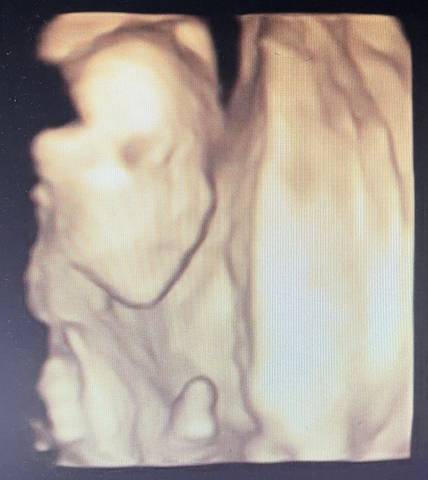

好奇是皮夹克还是小棉袄第一胎,现在22周多了,胎动比较早,大概16周就有胎动了。早期吃多了会吐,现在没啥事,肚子不显怀。刚做完大排畸,请各位大神帮忙看看男女。

可爱的孕妈,我们都是一样觉得好奇,这个确实没啥依据可参考的,就算B超有图片也只是一个宝宝的轮廓,祝您如愿!